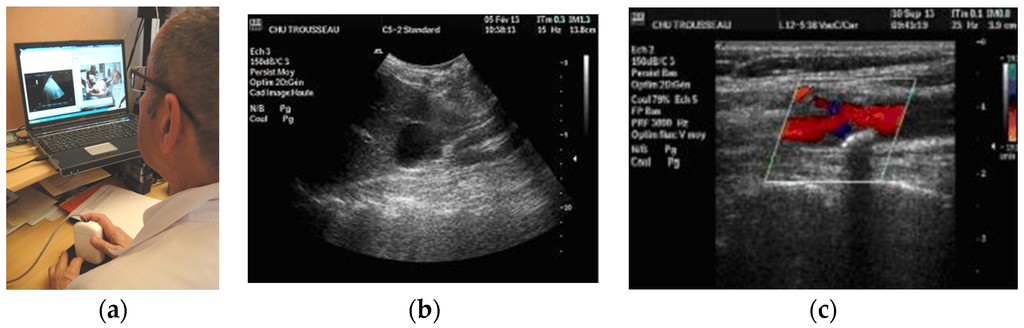

Figure 3. (a) General view of the isolated site with the MP held motionless on the patient by the non-sonographer operator (GP); (b) Probe with transducer tele-operated inside; (c) The expert with the dummy probe in hand, echograph function/settings teleoperation keyboard, and screen with ambient video and echographic view.

The three tele-echography methods used included: (a) a teleoperated robotic arm (RA) holding an ultrasound probe; (b) a teleoperated echograph with a motorized probe system (MP); and (c) remote guidance (RG). The RA (Figure 1) system consisted of a large structure that held a standard ultrasound probe. From the expert center (Figure 2), a trained sonographer performed the tele-echography examination by manipulating a dummy probe which teleoperated the robotic arm [1,3]. Throughout the examination, the non-sonographer operator at the patient site was required to position the robotic arm over the patient and to adjust the echograph functions and settings as directed by the trained sonographer. The second system of tele-echography, MP, consisted of a modified commercial echograph with motorized probes [2]. The ultrasound probes used for this system contained internal motors to tilt and rotate the probe transducer which the trained sonographer teleoperated from the expert center (Figure 3 and Figure 4). In addition to controlling the probe orientation, the echograph used for this system was modified to allow for the teleoperation of settings and functions. The final system of remote echography evaluated utilized RG (Figure 5) [5,6,7]. For this system, the non-sonographer (GP) had the probe in hand and performed the echographic examination as directed by a trained sonographer via videoconference.

Both teleoperated methods acted as an extension of the expert sonographer’s arm and hand, allowing the expert to tilt the probe (RA) or transducer (MP) ±55° from the vertical direction and to rotate the probe by ±180°. However, the MP was found to be more ergonomic and easier to move, allowing small translational movements (1–2 cm) and changes in the pressure of the probe against the patient’s skin, resulting in better image quality and reduced examination times.

Advancements in ultrasound probe technology lead to the recent development of the teleoperated motorized probe system. Much smaller and lighter than the RA (430 cm3, 400 g), the non-sonographer operators (GPs) found the MP system much easier to maneuver which resulted in shorter examination times. In addition, the low weight and general maneuverability of the motorized probes allowed for imaging along the side, and under the costal border of the patient, providing access to different acoustic windows without requiring the patient to change body position. As the MP system is limited by the availability of the specifically designed motorized probes, the probes constructed for the MP system were multi-frequency (3–5 MHz, and 5–15 MHz) to increase functionality. In contrast, the RA system could be modified to use a wide range of conventional ultrasound probes. However, due to its complex robotic technology, the RA system is much larger and more expensive than the MP system (50% higher cost). In the current study period, the medical professionals at the patient site and the trained sonographer did not have the option to choose between the RA and the MP systems as they were not available during the same time periods. However, after using each system for a minimum of six months, both medical professionals and patients expressed a preference for the MP method.

As with deep organ assessments, RG was not suited to the examination of superficial organs. The non-sonographer operators at the patient site were not capable of performing the fine probe adjustments necessary to obtain the quality of images in different planes necessary for diagnoses. It should be noted that to perform echography examinations, sonographers require extensive training over a six-month period for each organ group to be assessed, imaging approximately 8 h per day. Thus, only an expert sonographer is capable of quickly scanning the inside of the organs for diagnoses. However, with training, the non-sonographer operator was able to obtain images for assessments of superficial vessels which are easier targets.